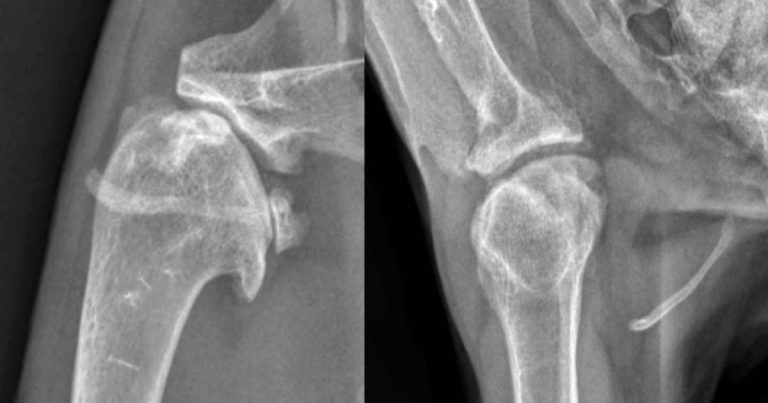

Figure 1. Mediolateral and craniocaudal radiographs of the shoulder of a 10-year-old cat presenting with moderate thoracic limb lameness associated with severe shoulder degenerative joint disease.

Degenerative joint disease (DJD) is becoming well recognised as a common and significant problem affecting domestic cats (Figure 1).